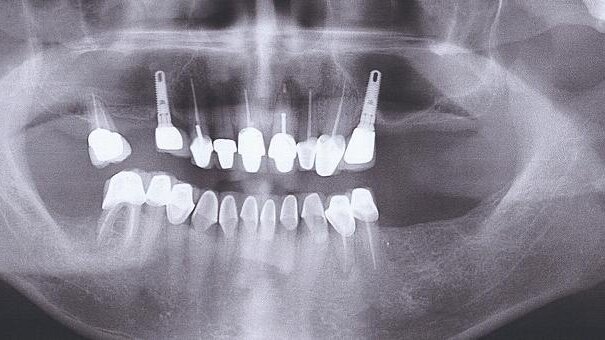

A literature and web search revealed several published reports of such complications, which include implant fractures (Fig. 1), impingement on adjacent teeth (Fig. 2), perforation of the lingual undercut (Fig. 3), sinus perforations (Fig. 4) and implants displaced into the maxillary sinus (Fig. 5). The clinical management associated with some of these complications is difficult at times and considered very invasive. Therefore, while the quantitative relationship between successful outcomes in dental implant treatment and CBCT-based dental imaging is unknown and awaits discovery through large prospective clinical trials, I strongly believe that using CBCT- and 3-D-based dental imaging is becoming a reliable procedure from a precautionary standpoint based on a series of recent preliminary clinical studies and case reports.

I also strongly believe that by taking 3-D CBCT images prior to placing dental implants, many of the above-mentioned complications can be circumvented .